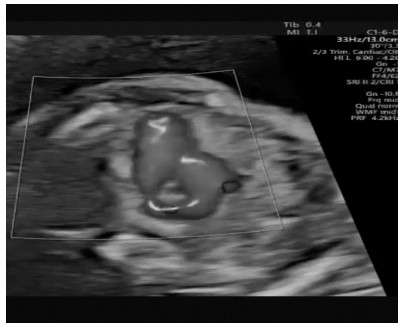

Paciente de 39 anos vai à consulta de pré-natal bastante assustada com o exame de ultrassom que fez no dia anterior. Relata que o médico tentou tranquilizá-la após o exame, mas não adiantou. Gesta 4, 3 abortos, hoje com 28 semanas. A imagem a seguir mostra um corte realizado na avaliação cardíaca do feto:

Com base nessas informações, assinale a alternativa que apresenta o diagnóstico mais provável nesse caso.